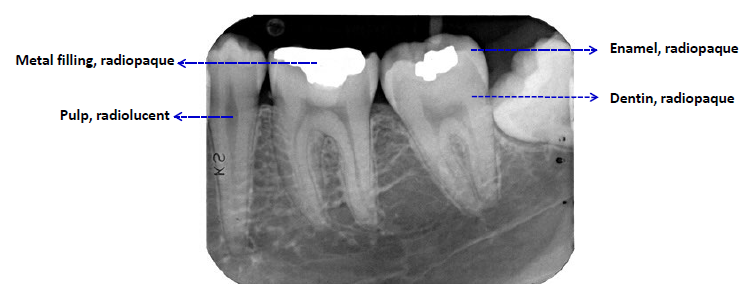

radiopaque or radiodense

stronger x-ray absorption

whiter/lighter apprearance

radiolucent

darker appearance (weaker x-ray absorption)

describing radiographic findings

localization: anatomic position, localized vs generalized, unilateral vs bilateral, single or multi

shape: round, ovoid, scalloped, irregular, etc

periphery (border): well defined vs poorly defined (invasive and malignant tumors)

internal structure: radiolucent (unilocular or multilocular, radiopaque, or mixed RL/RO)

effects on surrounding structures: resorption of teeth or expansion of bone, or resorption of cortex